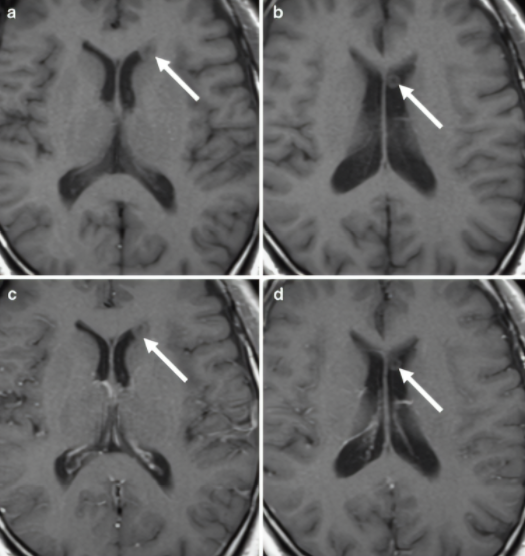

2 例单发侧脑室环状结节,增强检查均未见强化